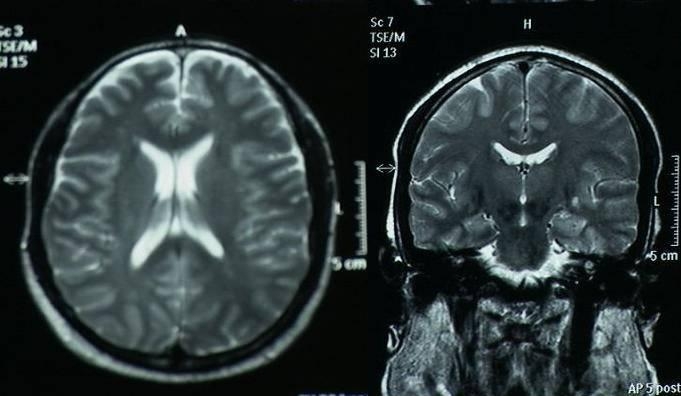

We present serial MRI studies in the case of a 45-year-old man who sustained an in hospital cardiac arrest and was successfully resuscitated after 25 minutes of cardiopulmonary resuscitation. Five years after the cardiac arrest he remains in a persistent vegetative state. Serial MRI studies (Fig 1 immediately and Fig 2 after 3 years and Fig 3 after 5 years of cardiac arrest) indicate ongoing cerebral atrophy and highlight the delayed effects of an initial anoxic injury.

Serial MRI axial and coronal sections studies (Fig 1 immediately and Fig 2 after 3 years and Fig 3 after 5 years of cardiac arrest) indicate ongoing cerebral atrophy and highlight the delayed effects of an initial anoxic injury.